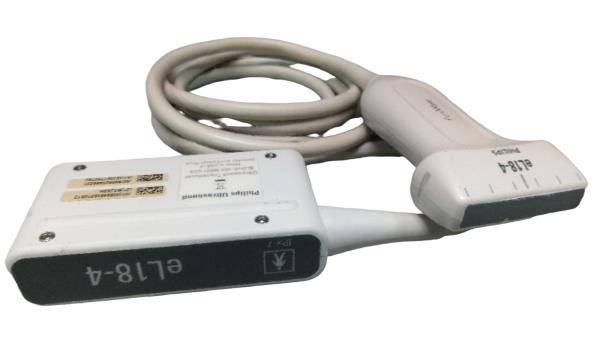

Save $ 179.82

DIAGNOSTIC ULTRASOUND MACHINES FOR SALE

Philips S7-2 Ultrasound TEE Probe (54DM)

Sale price$ 819.18

Regular price$ 999.00